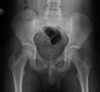

5

Intracapsular NOF